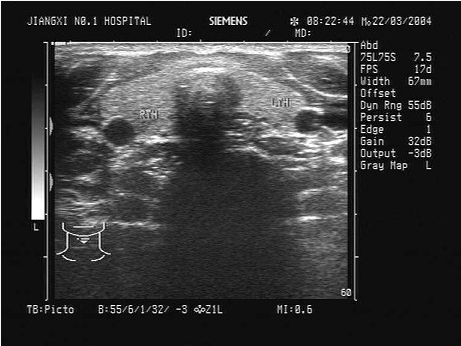

临床资料:女性,25岁,自述心悸,多汗,食欲亢进,体重减轻6个月余,发现颈部增粗1周。临床物理检查:甲状腺对称性增大,随吞咽上下运动,听诊有血管杂音。超声综合描述:双侧甲状腺增大,回声减低,明显不均,内未见囊实性肿物,CDFI:内可见丰富动静脉血流信号,呈"火海"征。见下图及彩图。

超声提示()。

A.结节性甲状腺肿

B.毒性甲状腺肿(原发性甲状腺功能亢进)

C.甲状腺腺瘤

D.甲状腺正常声像图